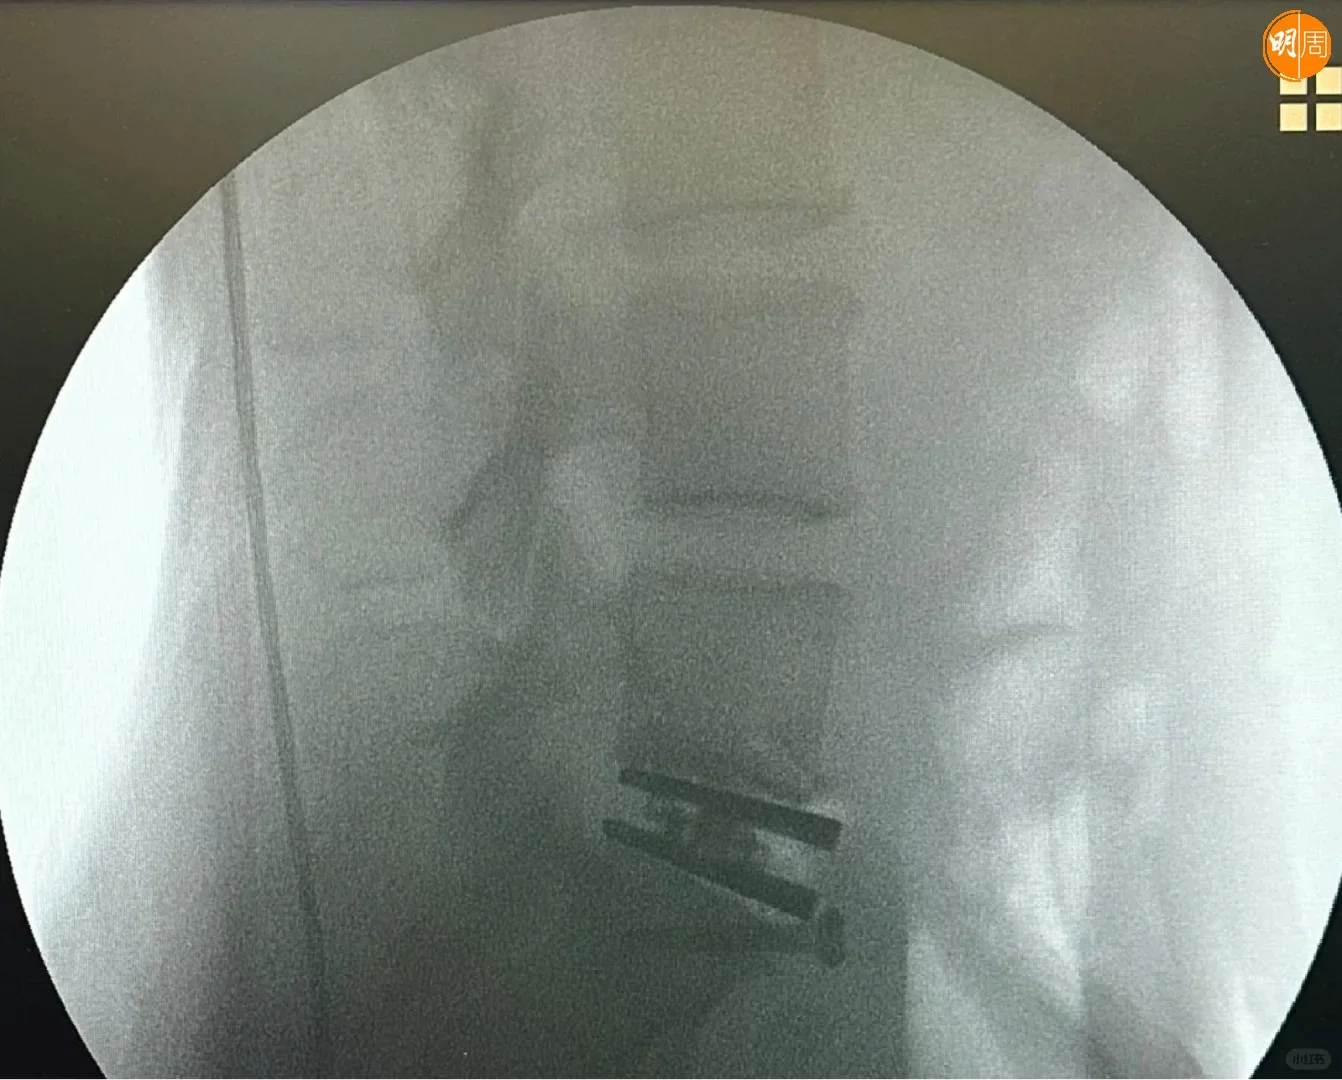

徐濠縈(阿徐)近日也入院做手術,昨晚(24日)阿徐在社交平台貼出X光照片,以及在手術室和醫護人合照,相中見阿徐露笑容,神情輕鬆,同時她上載花束及營養品等照片,此外,亦見到「加油!媽媽」的祝福句,似是囡囡陳康堤送給媽媽的打氣語句。

阿徐留言表示,今次是她自生女後最重要的手術,自揭前年曾接受切除椎間盤部分的手術,但下背仍然疼痛不已。熱愛跑步的她又謂,這2年過得特別難,她要停止重量訓練,並影響到她的日常生活,每當打噴嚏時,都有劇痛感覺,她的醫生建議做椎間盤置換手術。

阿徐今日(25日)亦有在小紅書發文,附加了臥在醫院病牀上雙手舉V的照片,她看來精神很好,身旁有到來探病的3大猛男謝霆鋒、馮德倫和劉浩龍,不知是否Eason負責揸機拍攝。阿徐以「手術成功」為題,並留言透露:「『人工椎間盤置換術』是一早安排今個6月份做的手術」、「康復時間需要幾個月」,網民都祝阿徐和Eason早日康復。